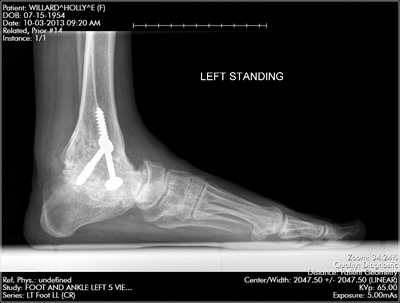

Thirty years ago, in 1987, I had fractured my left foot and ankle badly in a freak horseback riding accident. My ankle was repaired with the warning that I may never walk normally ever again. That said, I healed well and resumed my life. I was very active, riding my horse, walking my dogs, hiking, bike riding, etc. until 2009 when I had an acute onset of severe pain across the bottom of my foot. I went to a local orthopedic Doctor who ultimately said I needed to have my ankle fused. I went for a second opinion from an orthopedic surgeon at a prominent Boston hospital. He also agreed that I needed a fusion after trying a special foot and ankle brace to relieve the pain. He did not do much of a work up to pinpoint where the pain was coming from. I had my doubts about doing surgery, but over the past 20 years I had heard the same proclamation from several different orthopedic surgeons so I felt like maybe this was the treatment I needed. I was anxious to get back to my normal active life and with so many doctors stating that I would need to have my ankle fused I thought that maybe I had doubts because I was nervous.

This Doctor who did the surgery in 2010 said to me that "the surgery has an 85% success rate, so no need for more questions, it wasn't a brain surgery". I wish I had listened to that little voice in my head and kept asking questions. I had the fusion done, I was in horrific pain for 6 to 8 months, but the pain finally became "livable" and I resumed my not so active lifestyle. Three years after this surgery the joints in the rear part of my foot collapsed because of end stage arthritis. I could only walk with a removable boot cast on. I was in severe pain. I saw multiple orthopedic surgeons at multiple prominent Boston hospitals who all said that I needed another fusion surgery, but it might not work and I may just need an amputation. I was faced with the options of "live with the pain", try more surgery, or amputate, but none of these doctors even bothered to try and figure out exactly where the pain was coming from.

After doing the first fusion which failed badly and which I did because I was told "it should help so we should try it" I was not about to do another surgery unless someone could actually diagnose the source of my pain and none of the doctors from these "world renowned" Boston hospitals would even try to help me despite the fact that I could not walk and the pain was severe. Then, I found Dr. Leavitt. I called Dr. Leavitt's office and I got an appointment within one week. Dr. Leavitt started figuring out what was wrong at the very first visit. Dr. Leavitt did x-rays and a CT scan and gave me all the results during this first visit and then I knew I had finally found the best orthopedist in Boston. I had multiple appointments over the next 6 to 8 weeks as Dr. Leavitt systematically diagnosed exactly where all the pain was coming from. He precisely pinpointed which joints needed to be fused and he diagnosed the source of the original pain across the bottom of my foot as a condition called Tarsal Tunnel Syndrome which is similar to Carpal Tunnel Syndrome only it's in the bottom of my foot not in my wrist.